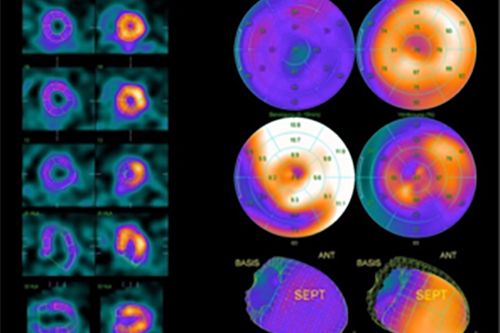

Die Myocardszintigraphie ist eine nuklearmedizinische Untersuchung der Durchblutung des Herzmuskels der linken Herzkammer. Hierbei werden die Durchblutungsverhältnisse sowohl unter Belastung als auch in Ruhe dargestellt. Durchblutungsstörungen des Herzmuskels werden in der Regel durch Verengungen der Herzkranzgefäße verursacht.

Nach einer Pause, in der Sie die selbst mitgebrachte fetthaltige Mahlzeit zu sich nehmen, werden dann spezielle Szintigramme mit einer Gammakamera mit 2 rotierenden Aufnahme-Köpfen aufgenommen. Es entstehen dreidimensionale Bilder des Herzmuskels (mit sogenannter SPECT – Technik). Dadurch wird eine genaue Beurteilung der Durchblutung in den einzelnen Herzmuskelarealen ermöglicht.